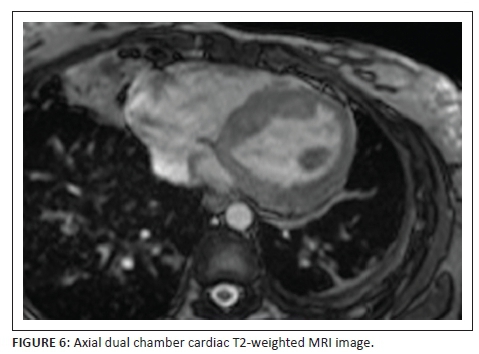

A 32-year-old lady presented with shortness of breath, (New York Heart Association [NYHA] grade 2-3), becoming progressively worse, associated with cough, chest pain and constitutional symptoms. She underwent extensive investigations shown in the series of images including chest radiograph, abdominal sonar, computed tomography of chest and abdomen as well as a cardiac magnetic resonance imaging study.

Describe the relevant imaging findings and formulate the most appropriate clinical diagnosis.